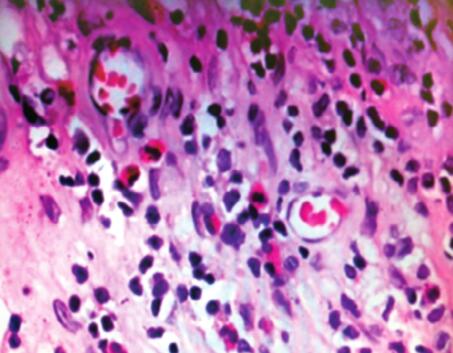

两次痰真菌培养阴性,真菌涂片未见菌丝;两次1,3-β-D-葡聚糖(-);血总IgE仅轻度升高;胸部CT影像学存在反复肺部浸润影,但未见中心性支气管扩张,故ABPA诊断依据不足。入院后患者自诉此次发作伴双上肢麻木,既往否认颈椎病史,头CT未见异常,遂行周围神经传导速检查,结果提示双上肢正中神经损害。并借阅外院4年前(2007年6月12日)鼻息肉手术病理片(图2),结果提示:慢性黏膜炎,伴血管外嗜酸性粒细胞浸润。

图2

ABPA影像学上也会出现反复肺部斑片状浸润影,但常沿支气管血管束分布,并伴中心性支气管扩张;ABPA化验检查也可有外周血嗜酸性粒细胞增高及总IgE浓度增高,但其总IgE升高明显,经常大于1000ng/ml;ABPA痰培养可有烟曲菌生长,可查到菌丝。结合患者临床表现和辅助检查,ABPA诊断依据不足。CSS为血管炎性疾病,可以累及多系统、多器官,最常见的累及外周神经,引起单发或多发神经病变,故本患者双上肢正中神经损害可能与CSS有关。结合其鼻息肉手术病理明确提示存在血管外嗜酸性粒细胞集聚,进一步证实CSS诊断。